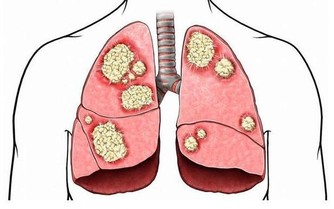

喜、怒、憂、思、悲、恐、驚七種情志變化,反映著機體的精神狀態。七情能正常表達則身體健康,七情過度表達則直接傷及五臟:過怒傷肝,過喜傷心,思慮過度傷脾,過度悲憂傷肺,驚恐過度傷腎。因此,對於日常產生的各種情緒,能正確對待,善於調節,才是健康的表現。